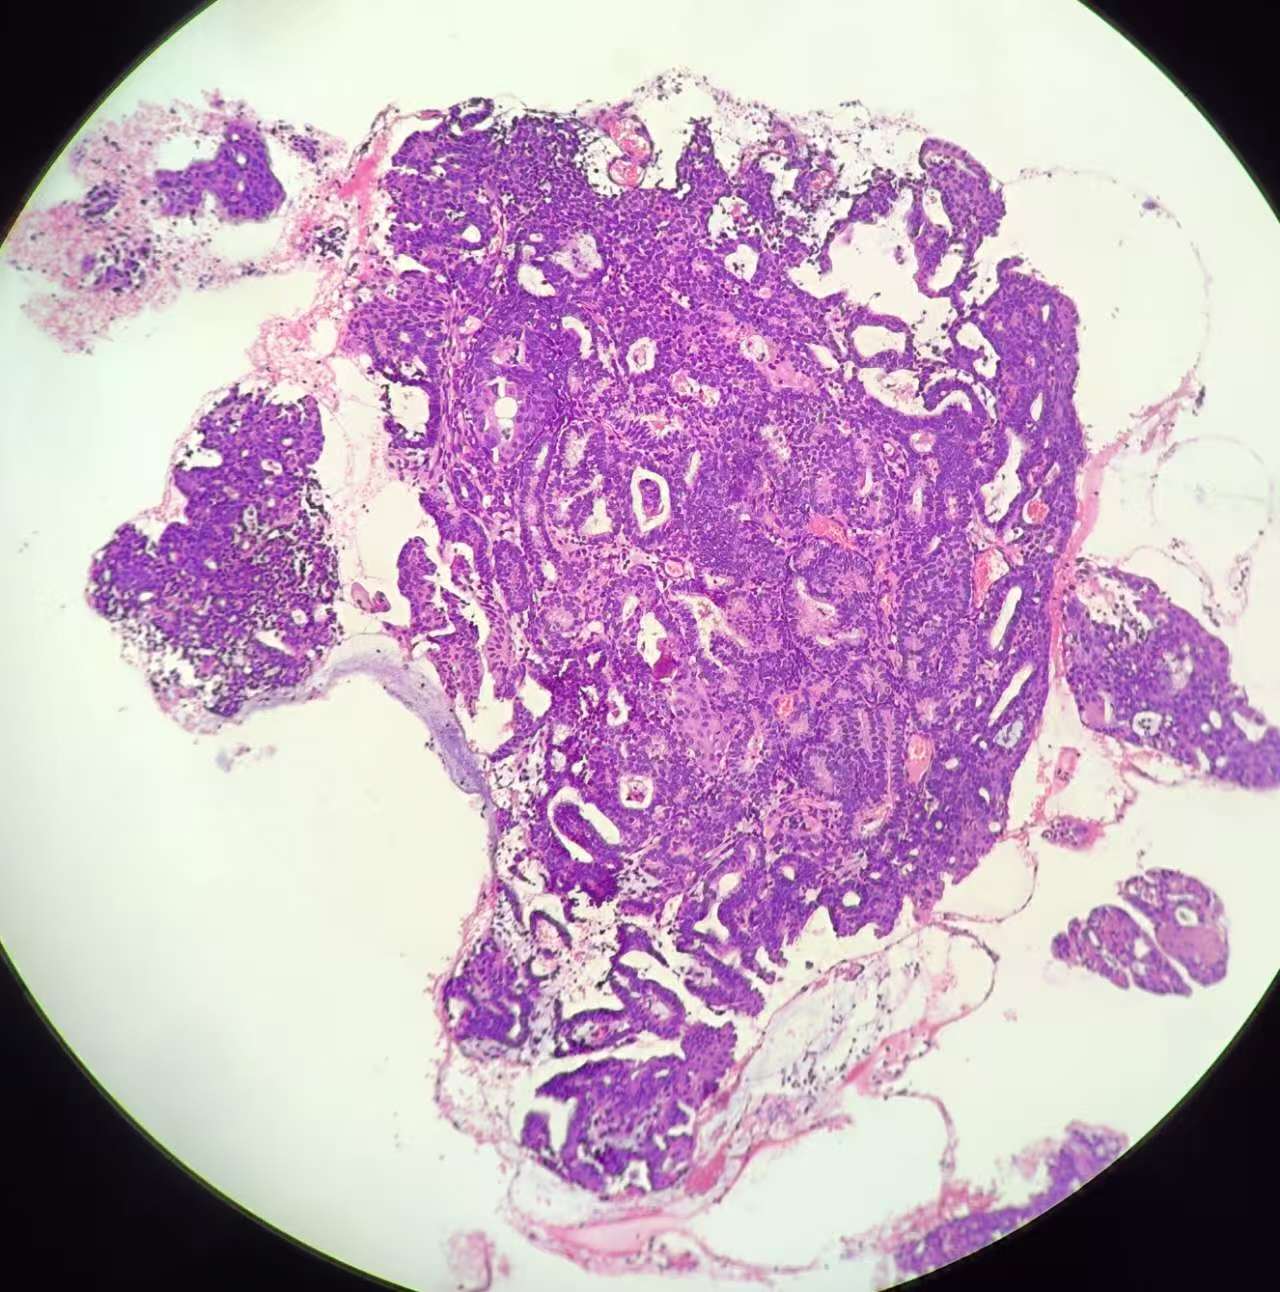

性别

女

年龄

51岁

临床诊断

子宫 内膜息肉?

一般病史

绝经三年,近期阴道出血,宫腔镜见后壁槽杂样组织,质脆

标本名称

子宫内膜诊刮

大体所见

灰红碎组织1堆

复杂性增生?部分区域腺体融合似成实性,癌?局部内膜腺体鳞化还是宫颈鳞上皮病变(第1张图和最后一张)?

考虑子宫内膜样腺癌,伴有鳞状分化。